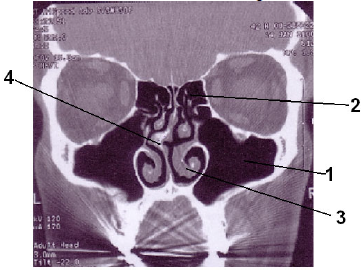

Assinale a alternativa que apresenta, na seqüência correta, as estruturas anatômicas identificadas na imagem abaixo.

1-seio frontal, 2-células etmoidais, 3-septo nasal, 4-concha nasal.

1-seio maxilar, 2-células etmoidais, 3-concha nasal, 4-septo nasal.

1-seio frontal, 2-seio esfenoidal, 3-concha nasal, 4-septo nasal.

1-seio maxilar, 2-seio frontal, 3-septo nasal, 4-concha nasal.